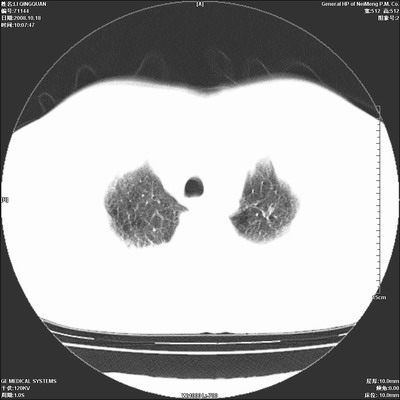

以下是引用duguo在2008-10-19 13:59:00的发言:[br]左肺上叶支气管狭窄,首先考虑中心型肺癌伴阻塞性肺炎\\肺不张.

以下是引用ybing在2008-10-19 12:58:00的发言:[br]左肺上叶阻塞性炎症-建议支气管镜进一步检查除外中央型肺癌

以下是引用随光逐影在2008-10-19 14:31:00的发言:[br]考虑左肺中央型肺癌并左肺上叶阻塞性肺炎,肺不张。